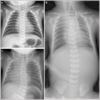

When are congenital diaphragmatic hernias usually detected? What would you see on CXR of baby with congenital diaphragmatic hernia?

* Diagnosed antenatally * See image for CXR